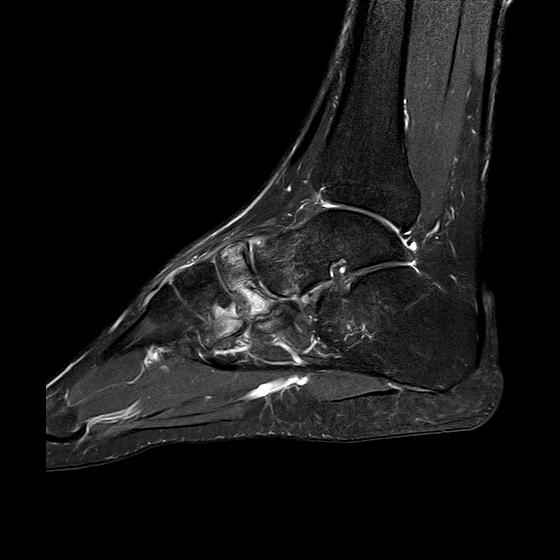

Дорогие коллеги,Мужчина 36 лет, пострадал около 8 месяцев назад в ДТП (водитель мотоцикла).

Подтаранный вывих лечили гипсовой лонгетой. Недиагностированным остался перелом ладьевидной кости, который беспокоит в настоящее время. Аваскулярный некроз кости, похоже. Добавил наиболее значимые снимки, на мой взгляд.

По данным снимкам однозначно сказать о некрозе ладьевидной кости нельзя. Типичные изменения при аваскулярном некрозе ладьевидной кости, как правило, начинаются в центральной её части с дальнейшим развитием коллапса. В данном случае в значительной степени пострадал таранно-ладьевидный сустав, вероятнее всего, именно это является причиной болевого синдрома. При отсутствии эффекта от физиотерапии и ношения ортопедической обуви в течение ближайших 6 месяцев придётся ставить вопрос о таранно-ладьевидном артродезе.